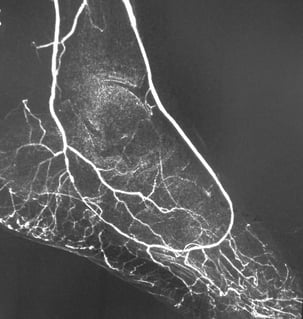

Our goal is simple: to make safer imaging the global standard of care. Through advanced CO2 delivery systems and continuous research collaboration, we support clinical decision-making where iodinated contrast agents carry unnecessary risk.